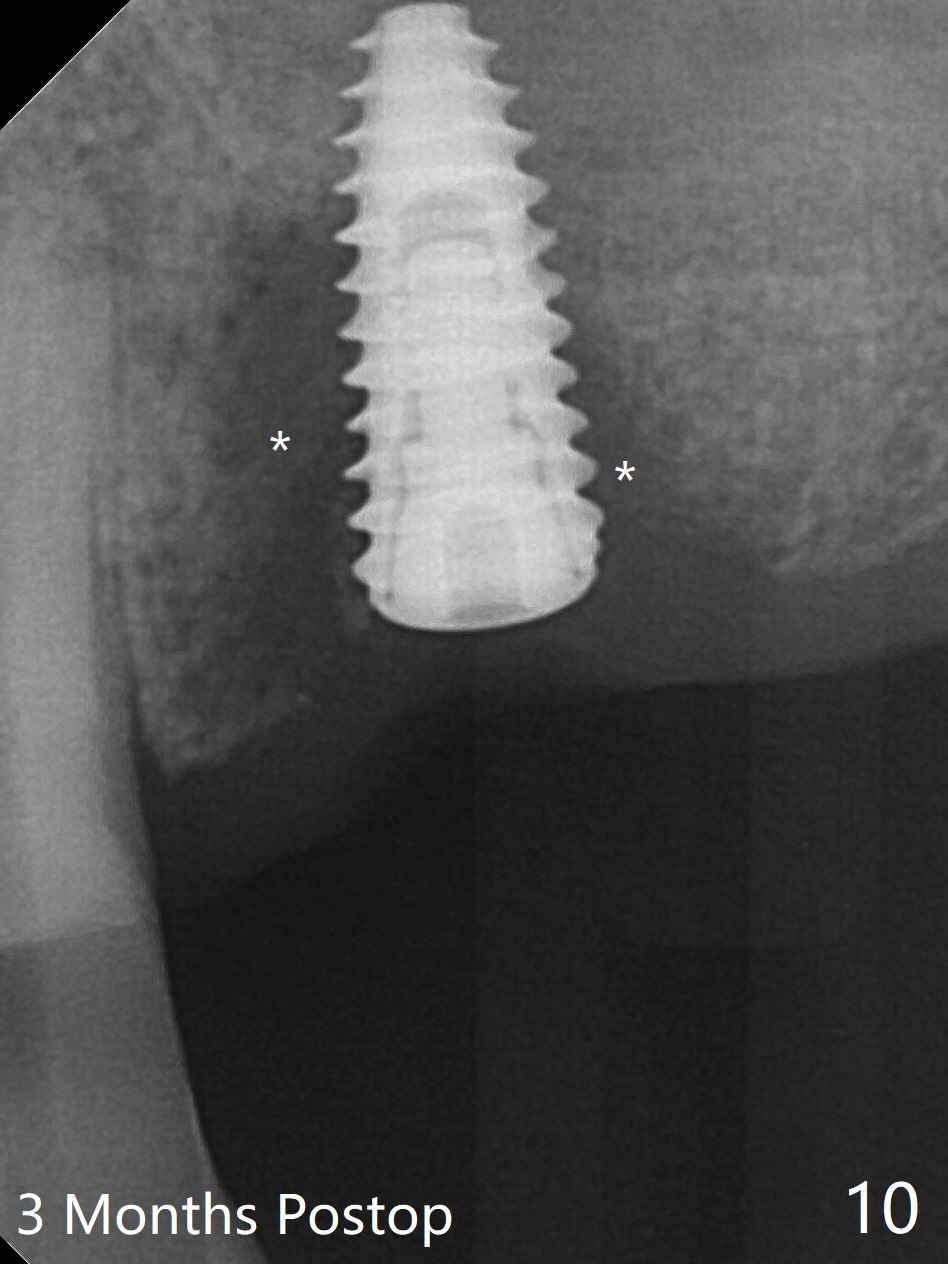

After a 4x10 mm implant is placed with fixture mounting (Fig.2 M) following sinus lift (*) at #12, osteotomy is initiated at #10 (Fig.1 (T: tube of surgical guide)). It appears that the drill (D) has good trajectory (between the Incisive Canal (red dashed line) and the canine root). The final position of the implant at #10 is acceptable (Fig.3). The implant at #12 is placed deeper (Fig.4 (arrow), as compared to Fig.2) because of clinically buccal superficial placement. The most critical challenge is anterior deep bite associated with posterior collapse. Periodontal dressing is applied. When the latter dislodges, there is minimal clearance for a provisional. Periodontal dressing is re-applied. The patient (smoker, partial edentulism with occlusal interference) returns for provisional nearly 1 month postop with chief complaint "something is lost in the back". In fact the healing abutment at #12 is lost with buccal granulation tissue (Fig.5). When a new abutment is seated, there is discomfort. When a healing screw is placed, it cannot be seated completely with two separate trials (Fig.6,7). Should we leave it as it is or open up for complete seating? It appears that the implant is loose. After preparation for clearance at #10, the abutment is retightened. It appears to turn with the underlying implant with discomfort. A 4x5 mm healing abutment is placed to reduce micro-movement. One week later, the infection at #12 dissolves with oral Amoxicillin (Fig.8). Due to limited occlusal clearance and implant tenderness when the abutment abutment is retightened, the cemented abutment is changed to a healing abutment. The implant at #10 seems to be osteointegrated, while the healing screw at #12 remains incomplete seating 3 months postop (Fig.9). The loose healing screw cannot be retightened securely, as there is bone loss around the implant 3 months postop (Fig.10 *). When a 4.5 mm x 15 degree 4 mm cuff angled abutment is placed, the mesiodistal trajectory improves (Fig.11), but there is no occlusal clearance (Fig.12). The latter would form when posterior support is established (Fig.13, either removable appliance (which the patient hates) or fixed one (finance)). Fig.14 shows the unhealed site of #12. Incision confirms the bone loss around the implant, which is removed. Although the sinus floor is absent, there is no membrane perforation. After debridement, allograft mixed with small amount of Osteogen is placed (Fig.15,16 G) and covered with Osteogen plug and 6-month membrane.